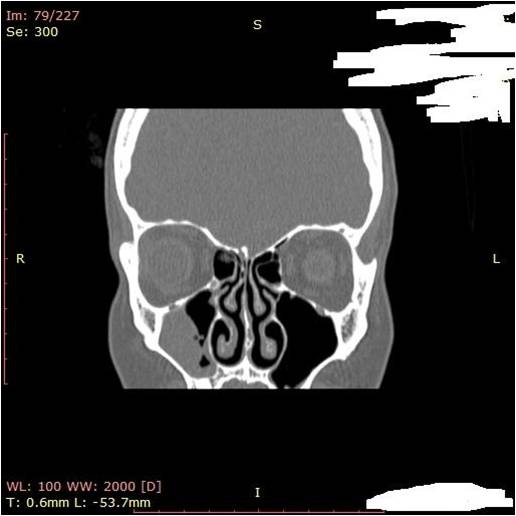

- Придаточные пазухи носа

- Кость верхней челюсти участвует в формировании придаточных пазух носа и глазницы

- Резонаторная роль, согрев и увлажнение воздуха в околоносовых пазухах

– в средний и верхний носовые ходы открываются отверстия околоносовых пазух